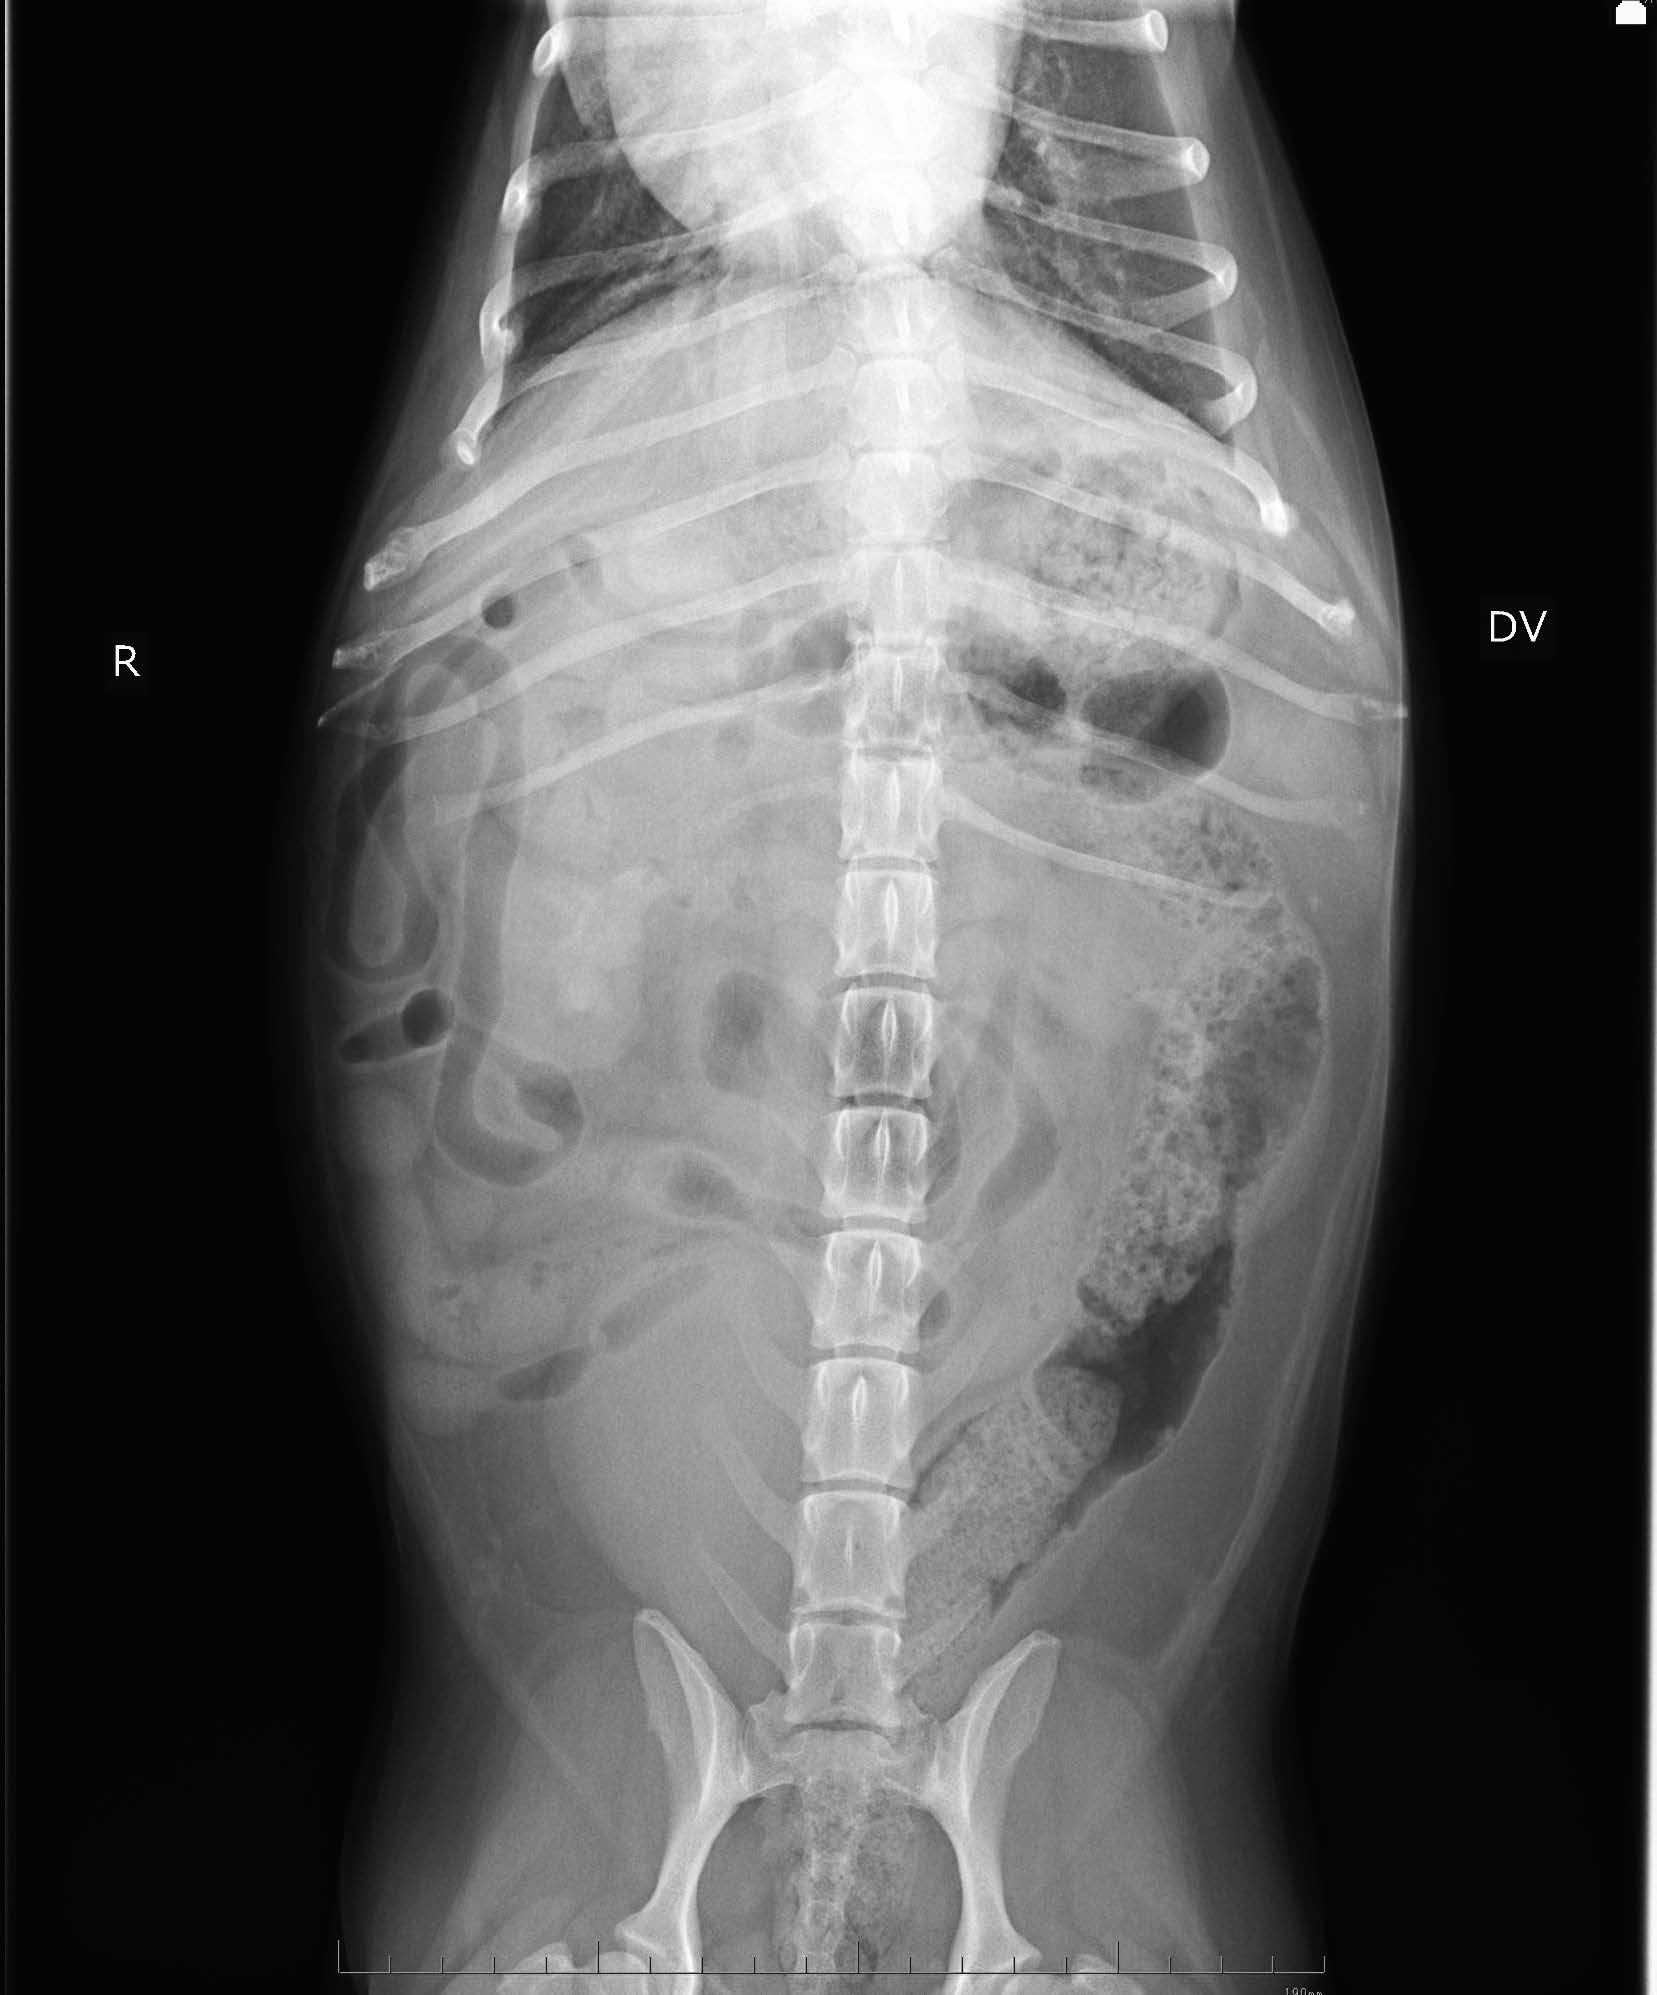

画像検査:腹部X 線検査では,肝サイズの低下と両腎にX 線不透過性の低い陰影が認められた(図1).腹部超音波検査では両側腎盂領域において,音響陰影を呈する高エコー構造物を認めた(図2).膀胱内には,高エコー源性の浮遊物及び沈渣が観察された.

図1 腹部X 線画像(仰臥位)

両側腎臓に軟部組織よりもわずかに不透過性が高い陰影を認める.